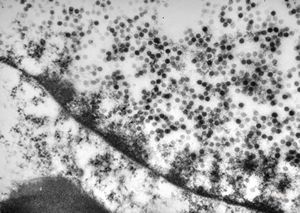

F, 24y. | molluscum contagiosum … virions

F, 24y. | molluscum contagiosum

F, 24y. | molluscum contagiosum

F, 7y. | molluscum contagiosum … virions

F, 7y. | molluscum contagiosum … virions

F, 24y. | molluscum contagiosum … virions